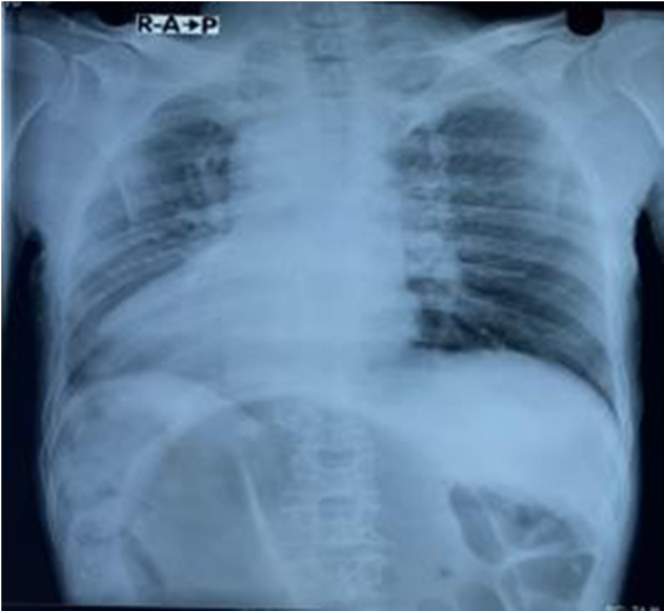

Case presentation: A 76-year-old male presented with abdominal pain and obstipation for 5 days. Clinical examination and imaging revealed signs of bowel obstruction and dextrocardia. Computed tomography (CT) scan abdomen confirmed sigmoid volvulus and situs inversus totalis. Emergency laparotomy revealed a 360-degree twisted, dilated sigmoid colon. Manual detorsion and excision of fibrous bands were performed. The patient recovered uneventfully.